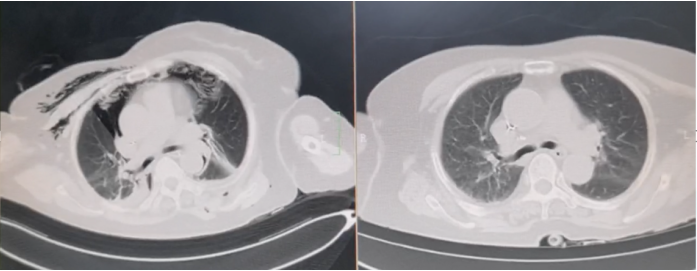

良性中心气道狭窄分为结构性和动力性(6种类型),结构性狭窄包括:管腔内生长(1型),外源性压迫(2型),瘢痕孪缩(3型),扭曲变形(4型);动力性狭窄包括:气道膜部向内膨出(5型),气道软化(6型)。对于动力性狭窄,应考虑用力呼气时的状态,通过操作者的判断,定出最合适、最接近的狭窄程度。治疗方法的制定不仅与气道狭窄程度和长度有关,还与是否存在狭窄过渡段有关。狭窄长度的计算应包括过渡区域。良性气道狭窄形态学分类的诊断方法应通过支气管镜所见及放射学检查来确定。每一个狭窄都可以用4个数字来表示,分别代表部位、类型、狭窄程度、狭窄长度。如:1344代表声门下瘢痕性挛缩性狭窄、狭窄程度>75%、狭窄长度>5 cm,这是一种非常难以处理的良性气道狭窄;2311代表气管瘢痕性蹼状网眼狭窄、狭窄程度<25%、狭窄长度<1 cm,这是一种比较容易处理的良性气道狭窄。热消融技术(APC、电凝、激光)是治疗增生性气道腔内病变(如良性肿瘤和单纯肉芽)的简单、快速的方法。但在治疗瘢痕狭窄病变时,其本身可对气道造成更重、更大范围的损伤,引起更为严重的肉芽组织增生和瘢痕形成,从而导致复发率高,且治疗次数的增加可导致狭窄病变范围增大并最终破坏软骨,导致气道塌陷,使患者彻底失去治愈的机会。电凝和APC仅适合管腔内生长的1型良性中心气道狭窄,并不适合其他类型良性中心气道狭窄的治疗。即便如此,基底部的处理也应避免使用此类治疗方法。针形电刀与气道黏膜接触面极小,不会造成损伤面扩大,瘢痕性气道狭窄的治疗宜选用针形电刀进行切割、松解。因激光也有切割的作用,因此也可选用激光治疗,钬激光、铥激光控制烧灼深度最浅可达0.4 mm,因此更适合良性瘢痕增生性气道狭窄的治疗。冷冻治疗分为冷冻切除(简称冻切,cryoextraction)及冷冻消融(简称冻融,cryoablation)。对于腔内生长的病变可采用冻切治疗,由于容易出血,其安全性不如热消融技术。对于瘢痕病变,冻切技术无法实施,则采用冻融治疗,冻融治疗不促进肉芽组织增生。与热消融相比,冷冻不易导致软骨损伤。通常在热消融治疗接近气道壁时或球囊扩张后采用冻融治疗处理剩余病变,有利于减轻瘢痕再狭窄发生的速度与程度。严重气道狭窄在开通气道前不要使用冻融,因其可引起气道水肿,加重气道狭窄,从而导致窒息。因此,冻融治疗后肺部体征监测及气管镜复查十分重要。机械扩张技术包括球囊扩张和硬质支气管镜扩张,并发症有气道撕裂、再狭窄、出血。(1)球囊扩张:是治疗瘢痕性气道狭窄最主要的技术,其优势是患者治疗后无明显的狭窄段延长,狭窄复发时再狭窄的程度比热消融治疗后轻得多,有利于维持气道复张的疗效。对气管黏膜损伤小,可以在软镜下应用,但需要中断通气。对于挛缩、韧性较强的瘢痕,可先用针形电刀进行切割以松解瘢痕;避免直接暴力球囊扩张,导致气道膜部的撕裂伤。(2)硬质支气管镜扩张:其优势是扩张时不需要中断通气,安全性更好。针对瘢痕肉芽组织增生导致介入治疗后的气道再狭窄,可采用气道狭窄部位局部应用药物的方法抑制瘢痕肉芽组织增生。介入治疗后气道再狭窄可选择的治疗药物有:糖皮质激素、丝裂霉素C、曲尼斯特、紫杉醇等。通过直接植入放射性物质(最常用铱-192)或经过可弯曲支气管镜近距离照射气道瘢痕肉芽组织,促使成纤维细胞凋亡。气道支架置入首选硅酮支架,禁用金属裸支架。支架治疗应作为良性气道狭窄最后选择的治疗技术,启动气道支架治疗的指征:①应用前述各种治疗方法疗效不佳,不能维持气道通畅;②在确定外科手术前临时放置;③外压性气道狭窄;④气道软化、塌陷且无法或不准备行外科手术治疗。病例1:17岁,女性,骨折术后肺炎插管,拔管后(2月14日)气道明显狭窄(图3)。2月15日评估:HR 113次/min,R 24次/min,静息下SpO2 97%(FiO2 50%),咳嗽及说话后喘鸣,有阵发性血氧下降。会诊后拟行急诊介入治疗。2月15日无痛气管镜示:声门下腔黄色及乳白色膜状坏死物,气管上段大量黄色坏死物并管腔重度阻塞,仅见小孔,以冷冻法清除坏死物后管腔通畅(图4)。术后气促明显改善,无需吸氧。病例2:77岁,女性,呼吸困难2个月,加重3天,于2023年12月2日入院(2023年9月气管插管,插管后20余天后拔管)。入院当天查体:HR 125次/min,R 30次/min,静息下SpO2 96%(高流量FiO2 30%),PaCO2 56 mmHg。患者术前影像如图5所示。12月3日查体:HR 140次/min,R 35次/min,BP 190/90 mmHg,SpO2 68%~75%(FiO2 100%),躁动不安,急查血气分析:PaCO2 89 mmHg。紧急床旁无创通气支持下气管镜:气管上段狭窄80%以上,较多黄白黏稠分泌物在狭窄口随呼吸摆动,予抽吸后SpO2升至98%,见狭窄处直径约3 mm,外径5.2 mm,软镜无法进入,遂置入导丝,10#球囊扩张多次,狭窄部位增宽,外径4 mm气管镜引导6.0号气管导管经口插管成功(图6)。插管后患者HR 98次/min,复查血气分析示PaCO2 41 mmHg,氧合指数300 mmHg以上。12月4日气管镜示:右鼻旁路进镜,缓慢退气管导管至声门,距声门3 cm处狭窄,直径7 mm,予12#球囊扩张1 min,2次,未见出血,扩张后直径约12 mm,地塞米松局部保留,气管导管复位(图7)。12月5日拔除气管导管。12月6日气管镜示:气管上段瘢痕狭窄(管径10~12 mm),少许膜状坏死、未见肉芽,予以清除坏死物,7点、11点冻融,术毕注入地塞米松5 mg(图8)。12月13日气管镜示:气管上段瘢痕狭窄(管径12 mm左右),少许膜状坏死、未见肉芽,予以清除坏死物,7点、11点冻融,术毕注入地塞米松5 mg(图9)。